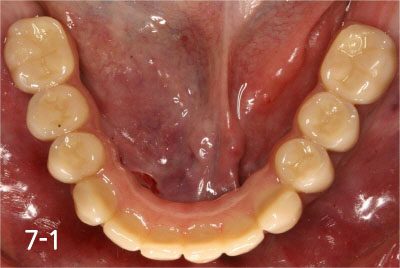

Totally edentulous status on lower jaw

Connection of temporary cylinder for provisional bridge

Provisional bridge to use right after placing implants

This is after bonding provisional bridge. Patient can have strong teeth in a few hours